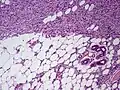

![]() | |

| Histopathological image of dermatofibrosarcoma protuberans. Local recurrence long after the first excision. H&E stain | |

Subcutaneous tissue infiltration (i.e. "honeycomb" growth pattern)